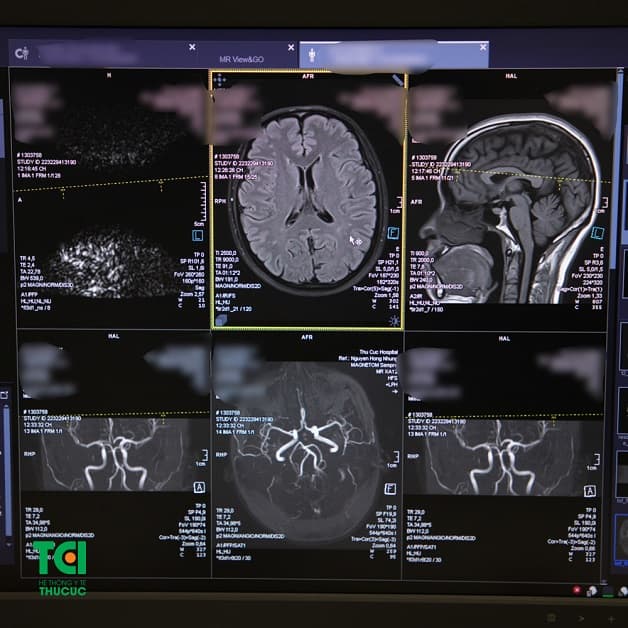

Hình ảnh chụp MRI não của bệnh nhân phát hiện thoái hóa não chất trắng, khi đi khám hậu COVID-19 tại Thu Cúc TCI.